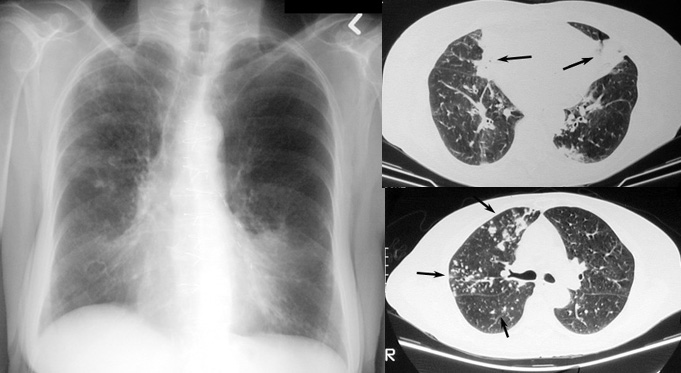

Mycobacterium Avium Intracellulare

• Scattered lung opacities, focal dilated bronchi, small nodules

• Characteristic involvement of right middle lobe and lingula